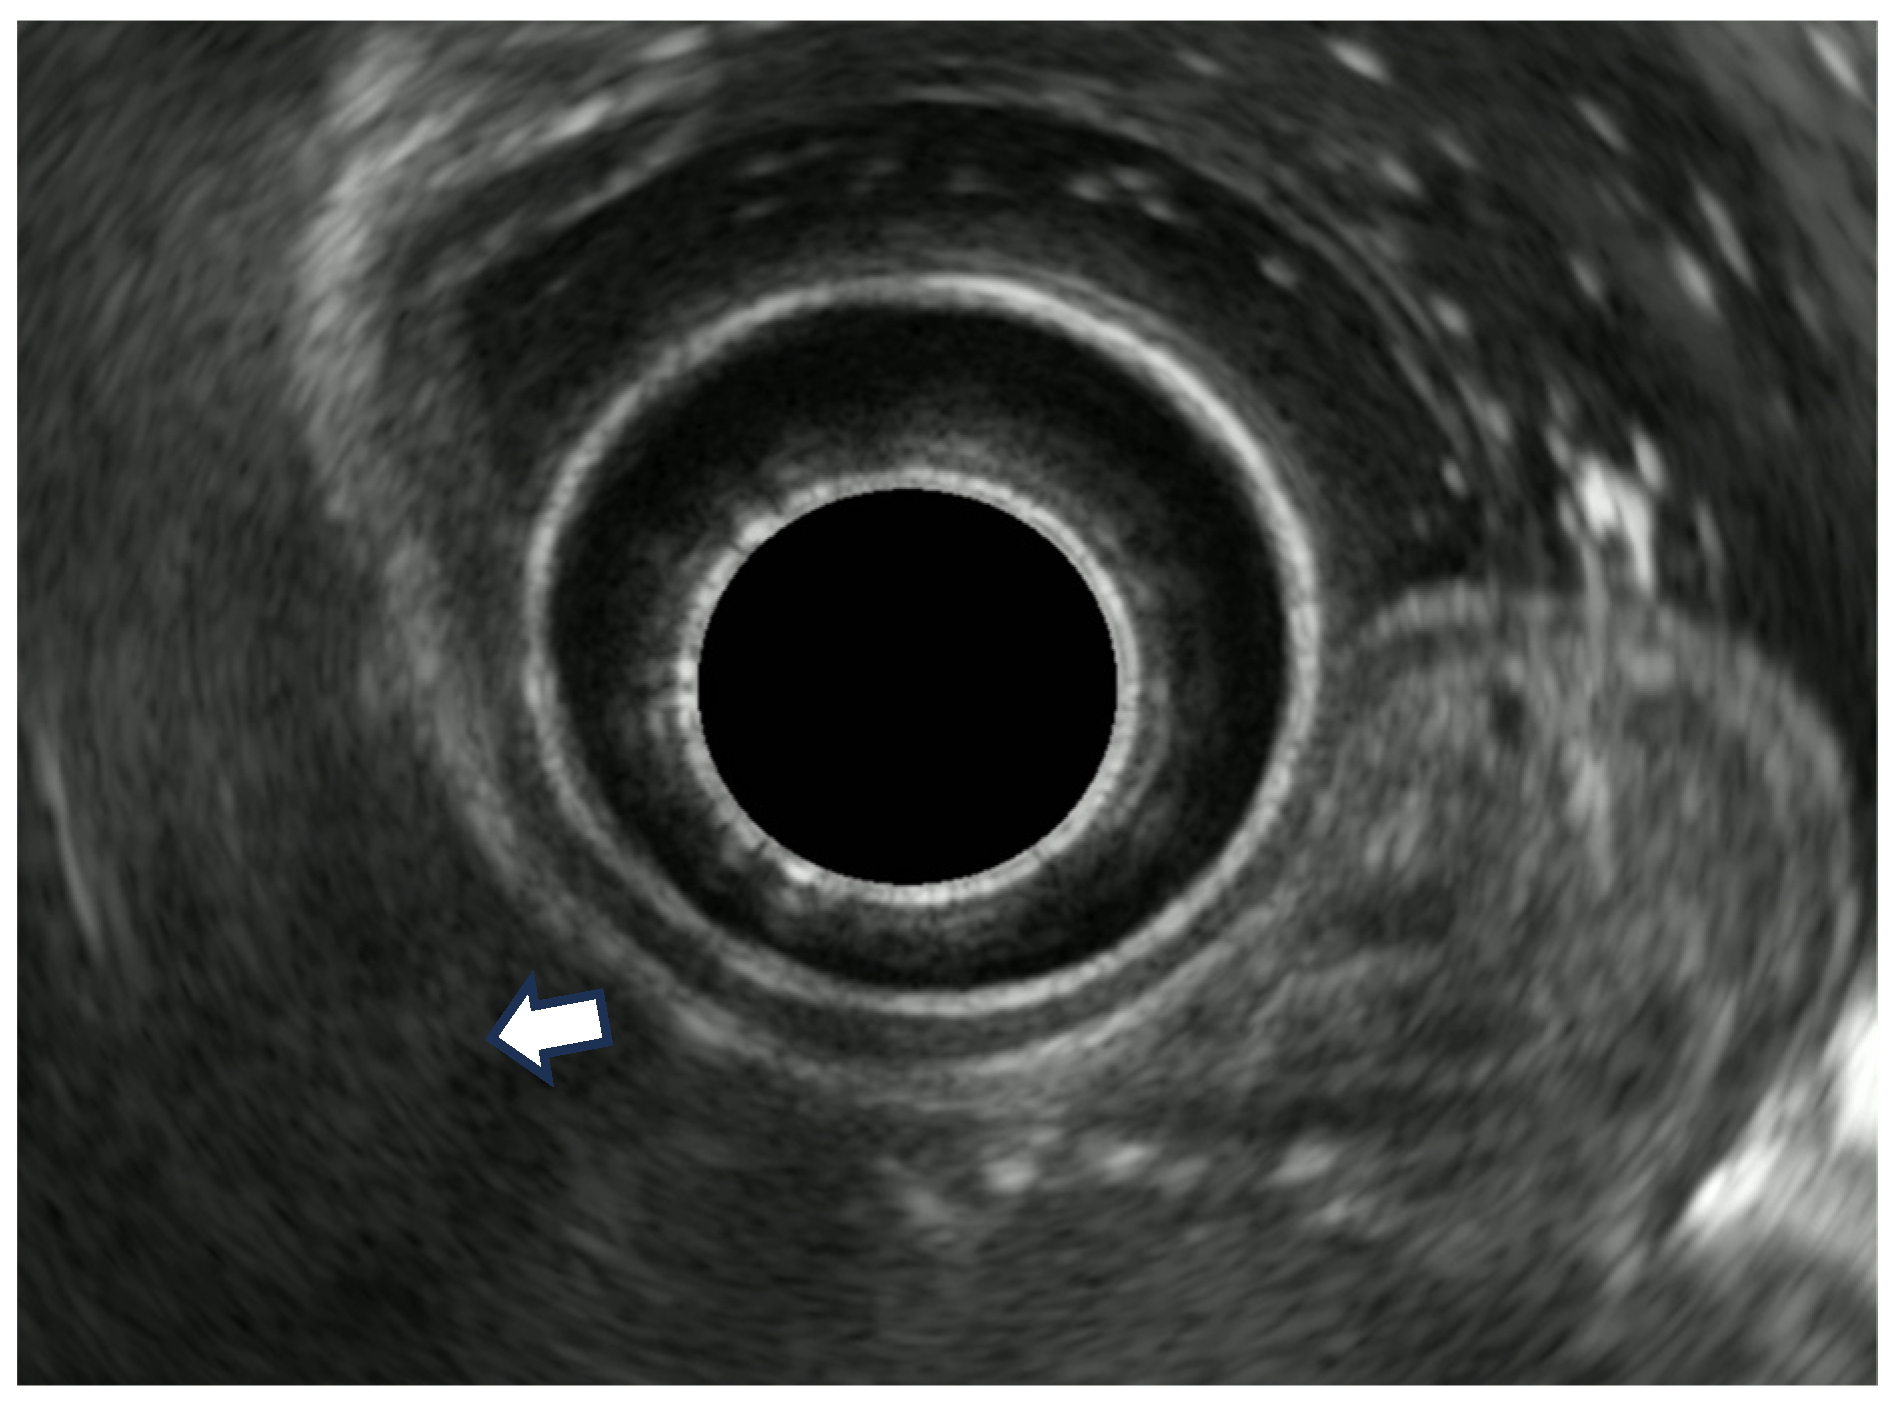

7. Endoscopic Rectal Ultrasound

8. Rectal Neoplastic Lesions

8.1. Rectal Superficial Cancer

8.2. Advanced Rectal Cancer